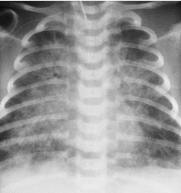

Das Atemnotsyndrom Frühgeborener (RDS: „respiratory distress syndrome“; syn: hyalines Membranensyndrom) stellte vor Einführung der Surfactantsubstitution die häufigste Todesursache der Neonatalperiode dar. Ungefähr 1% aller Neugeborenen erkrankt an einem RDS. Die Inzidenz steigt mit abnehmendem Gestationsalter: bis zu 60% der Frühgeborenen <30. Gestationswoche entwickeln ein RDS.

Pathogenese